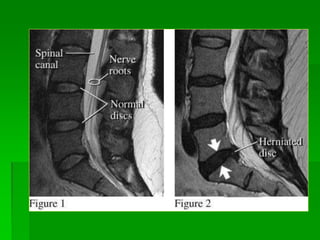

LỒI ĐĨA ĐỆM (bulging disc)

- Không phải là một dạng của thoát vị đĩa đệm.

- Bờ của đĩa đệm lồi ra > 50% của chu vi đĩa đệm bình thường.

 Protrusion: Bờ của đĩa đệm nhô ra nhỏ hơn 50% của chu vi đĩa đệm

bình thường và phần thoát vị có chiều rộng > chiều cao. Gồm:

- Focal protrsion: Bờ của đĩa đệm nhô ra nhỏ hơn 25% của chu

vi đĩa đệm bình thường .

- Broad-based or diffuse protrusion: Bờ của đĩa đệm nhô ra 25-

50% của chu vi đĩa đệm bình thường.

- Far lateral diffuse protrusion: thoát vị bên xa vào vùng lỗ liên

hợp hay ngoài lỗ liên hợp.

 Extrusion (with or without free fragment): Bờ của đĩa đệm nhô ra

< 50% của chu vi đĩa đệm bình thường và phần thoát vị có chiều rộng

< chiều cao.

THOÁT VỊ ĐĨA ĐỆM (herniation): gồm

Thoát vị đĩa đệm tầng L5-S1, chèn rễ S1(T)

Thoát vị đĩa đệm

vào lỗ liên hợp